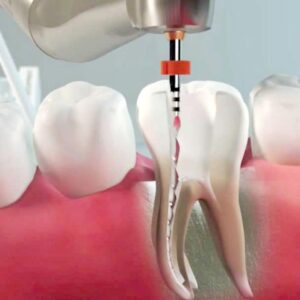

Endodonzia

L’endodonzia è la branca dell’odontoiatria che ha per oggetto i tessuti interni del dente, le patologie ed i trattamenti correlati. Questi tessuti possono ammalarsi o danneggiarsi a causa di carie, traumi o fratture . Il trattamento endodontico permette di salvare il dente curando il granuloma apicale , cioè l’ infiammazione cronica dei tessuti che circondano...

Ritrattamento in Endodonzia

Ritrattare Endodonticamente un dente è necessario quando : -la precedente cura è scorretta o incompleta -in presenza di lesioni periapicali o granulomi ,che in radiografia si determinano come aloni scuri intorno all’apice del dente. Di fronte a denti gravemente compromessi, che mostrano persistenza di lesione periapicale dopo terapie canalari ortograda e chirurgica, l’estrazione e la...